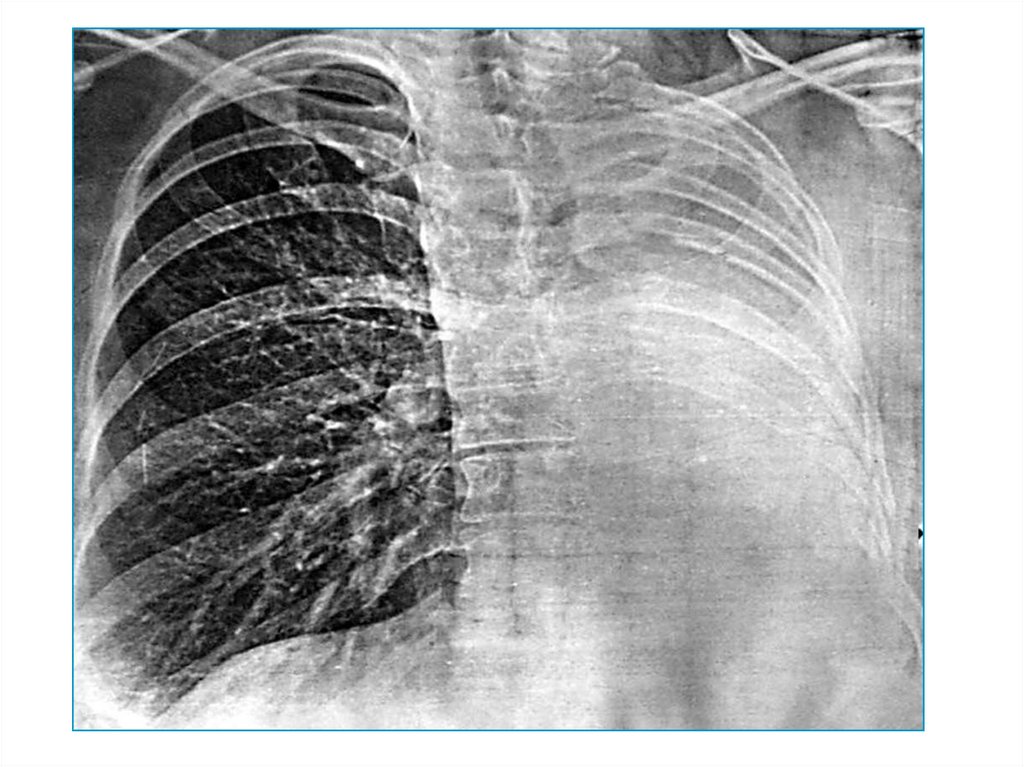

23. Компенсаторная эмфизема

В случае ателектаза/удаления другого легкого.

Видимая картина – тотальное односторнее

просветление легкого, смещение средостения в

другую сторону.